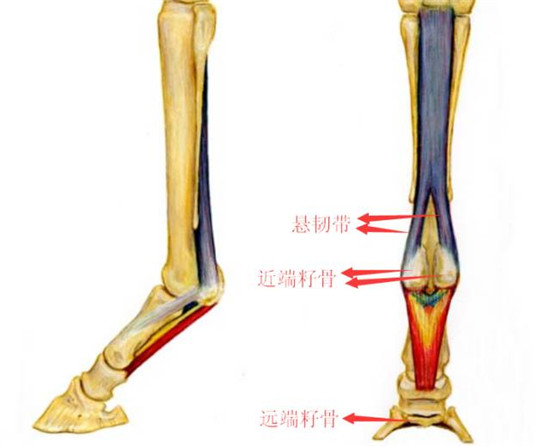

3.找到近端籽骨和远端籽骨

▲示意图(前肢)

籽骨是支持装置的一部分。悬韧带在球节部位走向分成两侧支,分别在两端近端籽骨侧面牵引。在马匹快速运动的过程中,球关节重复性过度伸展或者受外力作用,籽骨可发生疲劳性损伤或者外力损伤。常发于运动马匹,前肢多发。

▲近端籽骨和悬韧带